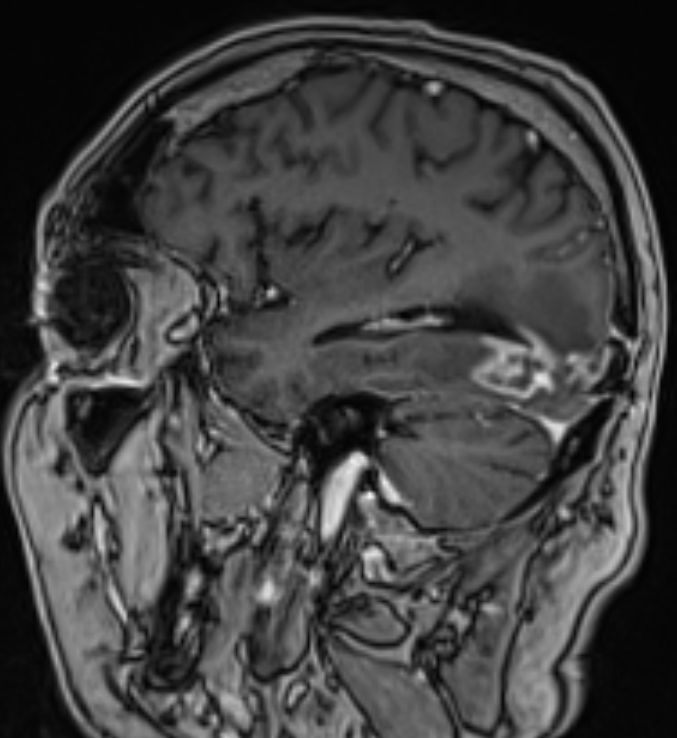

• 54-jähriger Mann, der vor 4 Jahren ein Adenokarzinom des rechten Lungenoberlappens cT4 cN1 M0 entwickelte

•  Cisplatin / Alimta - Chemotherapie, dann Radio –Chemotherapie 50Gy, 3 Zyklen simultan Cisplatin und Pemetrexed

• extrapleurale Oberlappenresektion,  Lymphadenektomie

• postoperatives Stadium ypT3 ypN0 L0 V0 G3

• adjuvante Bestrahlung der Thoraxwand rechts ED 3 Gy, GD 30 Gy

• vor 2 Jahren Metastase links parieto – occipital,  neurochirurgische Entfernung, Bestrahlung des Neurokraniums mit 30 Gy, ED 3 Gy

• vor 1 Jahr  Exstirpation einer Hirnmetaste links occipital, Bestrahlung des Hirnmetastasenbettes links occipital mit 40 Gy, ED 2 Gy

Die linke Spalte zeigt MRTs vor 7 Monaten, die rechte Spalte aktuelle MRTs.

Die MRTs zeigen eine Zunahme der Gadolinium-anreichernden Bezirke. Die Exzision erbrachte Großhirngewebe mit Anteilen einer Nekrose. Kein Tumorgewebe.